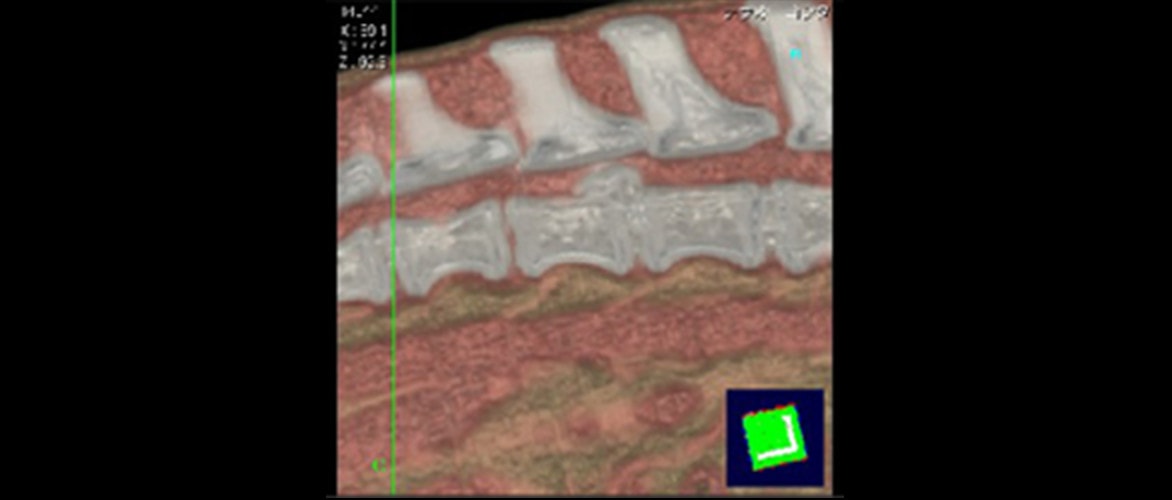

CT画像は冠状断面(輪切り)で見た断層画像です。CT撮影後その情報をコンピューター処理後、矢状断面に再構築した画像です。椎間板からの髄核物質が脊髄を圧迫しているのがよく分かります。CTで診断し、同時に手術することにより回復が早くなりました。